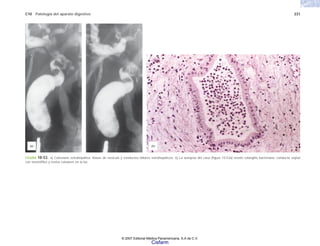

10 Patología general debeser conocimiento científico, debe pasar las pruebas más rigurosas que podamos imaginar, una y otra vez, hasta despojarlo de todos los sueños, deseos, esperanzas e intereses económicos y de otros tipos. Sólo entonces sirve para prevenir y curar las enfermedades. Sin el conocimiento científico de la enfermedad la medicina, la “buena” medicina, no es posible. LECTURAS ADICIONALES Pérez Tamayo, R. El concepto de enfermedad. Su evolución a través de la historia. México. El Colegio Nacional-Fondo de Cultura Eco- nómica. 1988. Pérez Tamayo, R. Historia de diez gigantes. México. El Colegio Nacio- nal. 1991. PérezTamayo, R. De la magia primitiva a la medicina moderna. México. Fondo de Cultura Económica. 1997. Patologi a_01_5R.indd 10 Patologi a_01_5R.indd 10 25/4/07 18:51:23 25/4/07 18:51:23 Cisfarm

• 11.